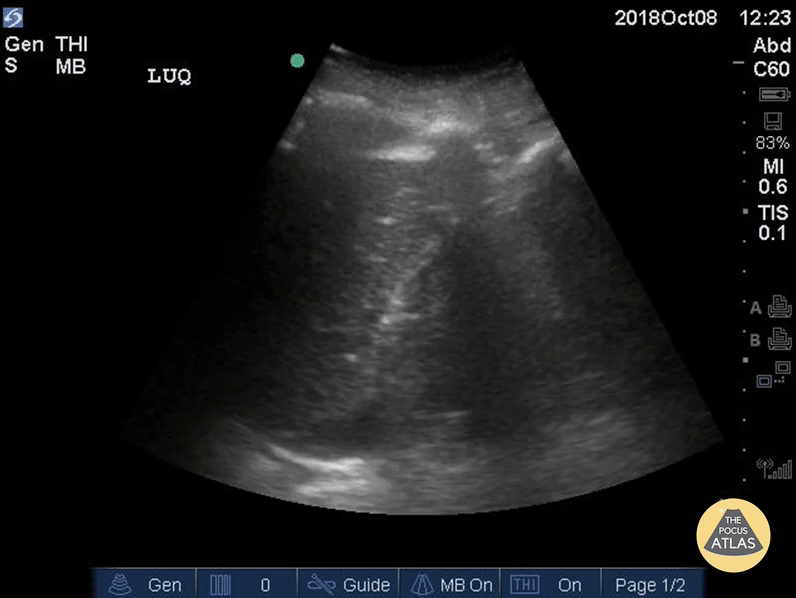

Trauma - Subtle Positive FAST - LUQ

Positive FAST exam demonstrating free fluid in the left upper quadrant. Spontaneous hemoperitoneum in an anticoagulated patient with a left ventricular assist device (LVAD). Dr. Elias Jaffa, MD